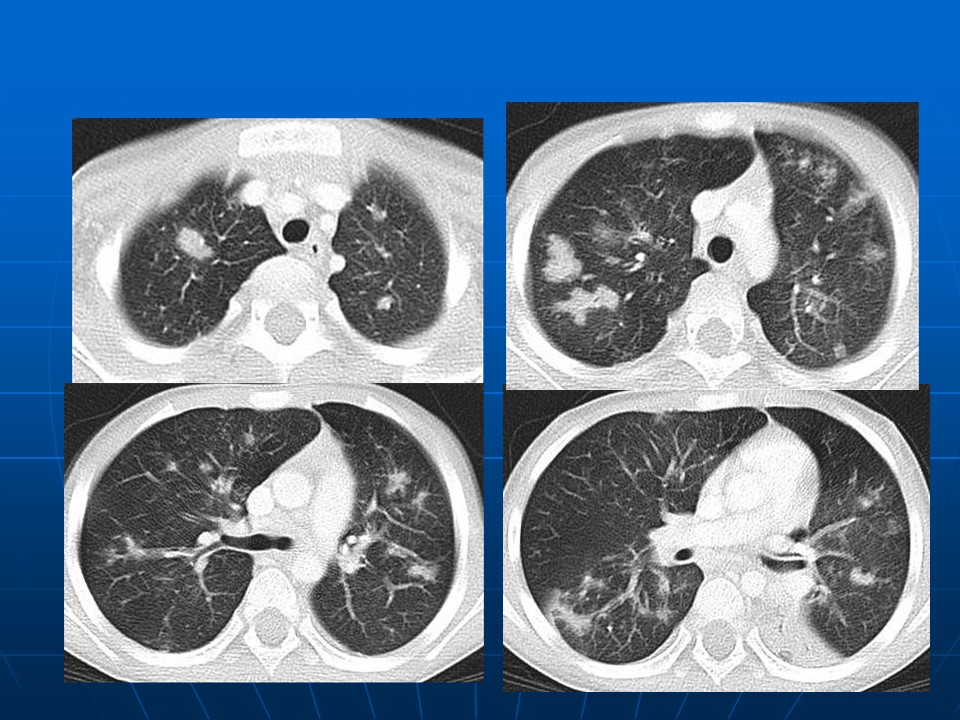

下一篇:【病例】肺动脉静脉畸形1例CT